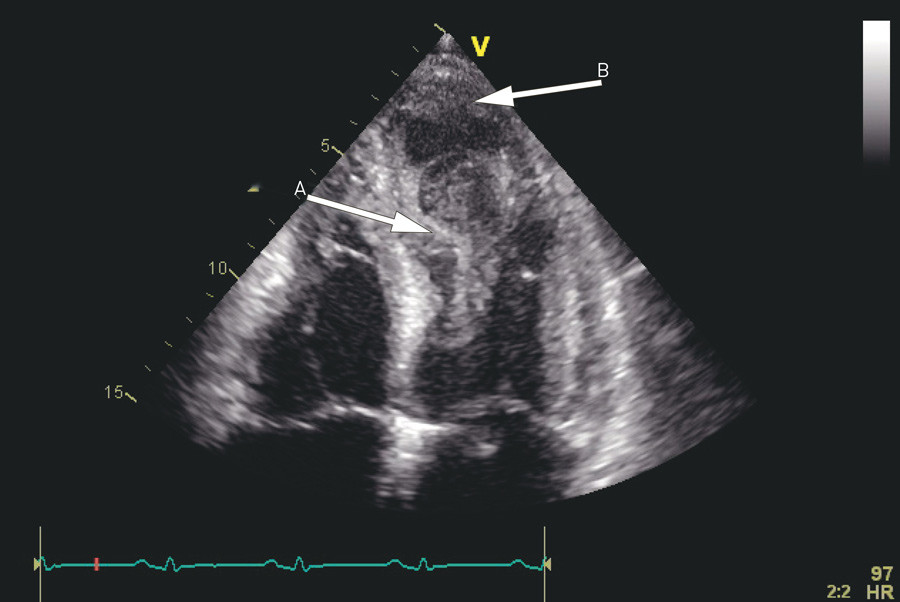

To dager etter overflyttingen viste ny ekkokardiografisk undersøkelse lett dilatasjon og betydelig redusert funksjon av både høyre og venstre ventrikkel. Venstre ventrikkels ejeksjonsfraksjon ble estimert til omtrent 25 % (normalt 55 – 70 %). Det var regionale kontraksjonsforstyrrelser fordelt over store deler av venstre ventrikkels myokard, og disse forandringene var ikke lokalisert apikalt, midtventrikulært eller basalt, slik man ser ved takotsubokardiomyopati.

Det ble ikke sett organiserte tromber, men det var betydelig spontankontrast i apikale halvdel av venstre ventrikkel. Det forelå moderat pulmonal hypertensjon (systolisk pulmonalarterietrykk 50 mm Hg, normalt < 30 mm Hg), og det var store regionale forskjeller i veggfortykkelse, uten at dette passet med koronare forsyningsområder (fig 3, video 1).

Pasienten hadde utviklet en alvorlig hjertesvikt med symptomer i hvile – New York Heart Association (NYHA) klasse IV. Det var beskjedne funn ved koronar angiografi, og de kunne ikke forklare den betydelige reduksjonen i venstre ventrikkels funksjon. De regionale forskjellene i kontraktilitet passet heller ikke med takotsubokardiomyopati. EKG med ST-T-forandringer og høyt troponin I-nivå gjorde at man nå mistenkte myokarditt. Ticagrelor ble seponert, mens pasienten fortsatt fikk acetylsalisylsyre og statin på grunn av påviste veggforandringer i koronararteriene.